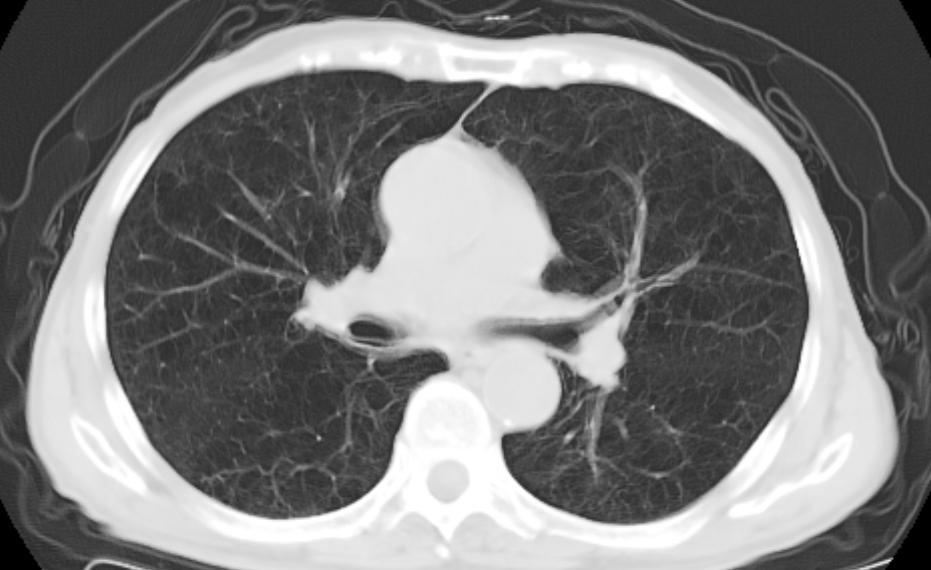

血气分析提示:轻度低氧血症。胸部CT提示:肺气肿、双肺慢性感染。故结合该患者病史 (近期无呼吸困难加重、明显痰量增多或浓痰) 、肺功能检查、胸部CT检查,明确诊断为: 慢性阻塞性肺疾病稳定期,目前该患者已达慢性阻塞性肺疾病III级,C组 ,故药物选择应为吸入激素及支气管扩制剂的联合治疗,选择布地奈德福莫特罗粉吸入剂吸入治疗,并嘱该患者戒烟。

图片来源 :讲述者提供